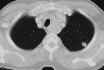

Metastasen

Eine pulmonale Metastasierung ist häufig insbesondere bei Colon-, Pankreas-, Mamma-, Nierenzell-, Prostatakarzinomen und dem malignen Melanom. Lungenmetastasen stellen sich in der Computertomographie als meist multiple, weichteildichte Rundherde dar, die ab einer Grösse von ca. 2 mm computertomographisch nachweisbar sind. Sie treten hydrostatisch bedingt dorsobasal häufiger auf.

metastases of the lung